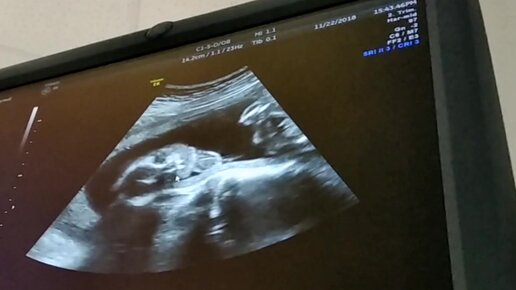

Малышка машет маме и танцует в утробе.